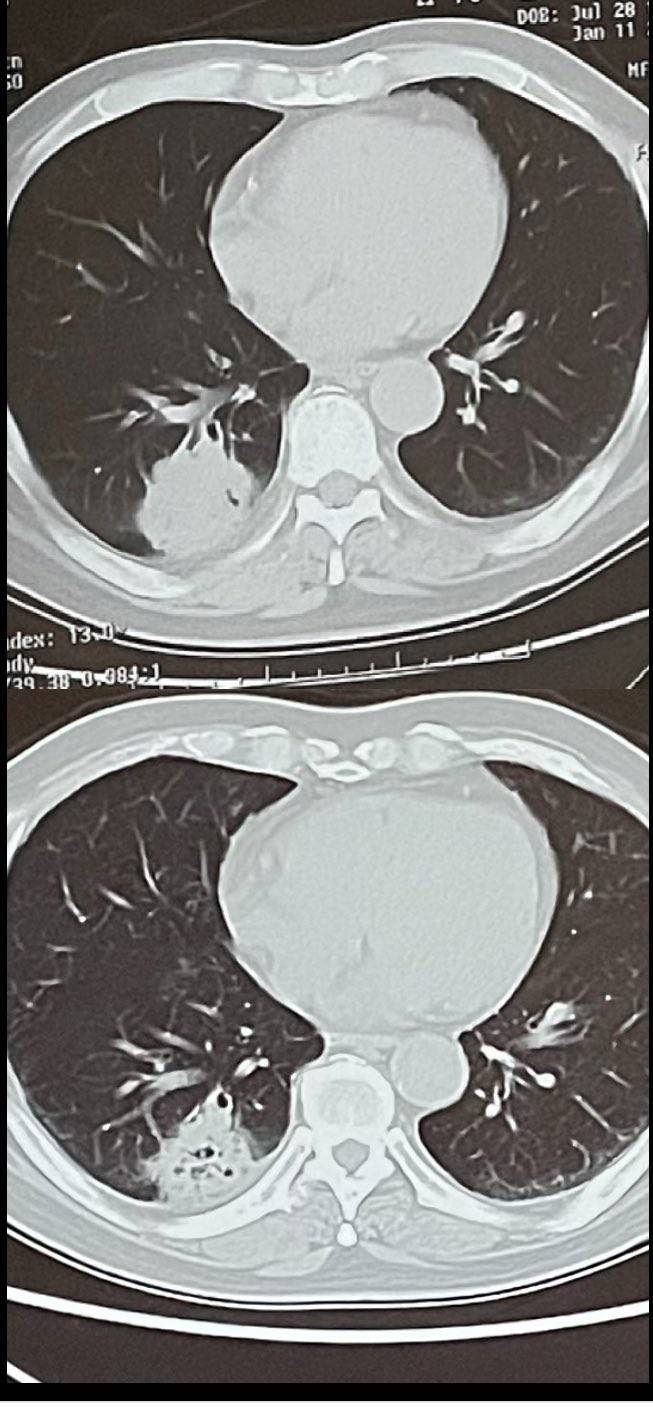

空洞就是在坏死,接下来会缩小的,我爸之前就这样